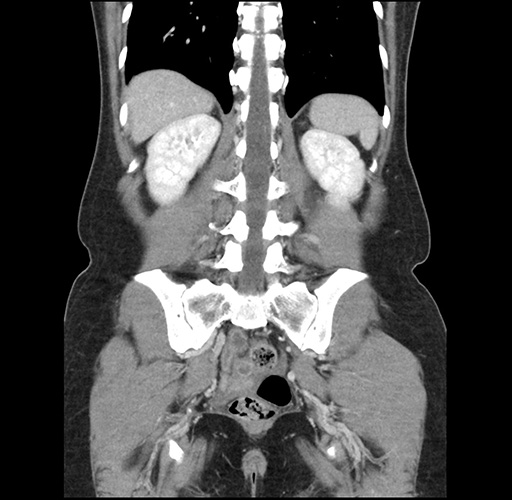

Imaging Analysis

Look through the patient's CT scan to identify any areas of concern for the necessary procedure.

Based on your CT findings, which issue(s) would give reason for "planned slowing down moment(s)" in this case?